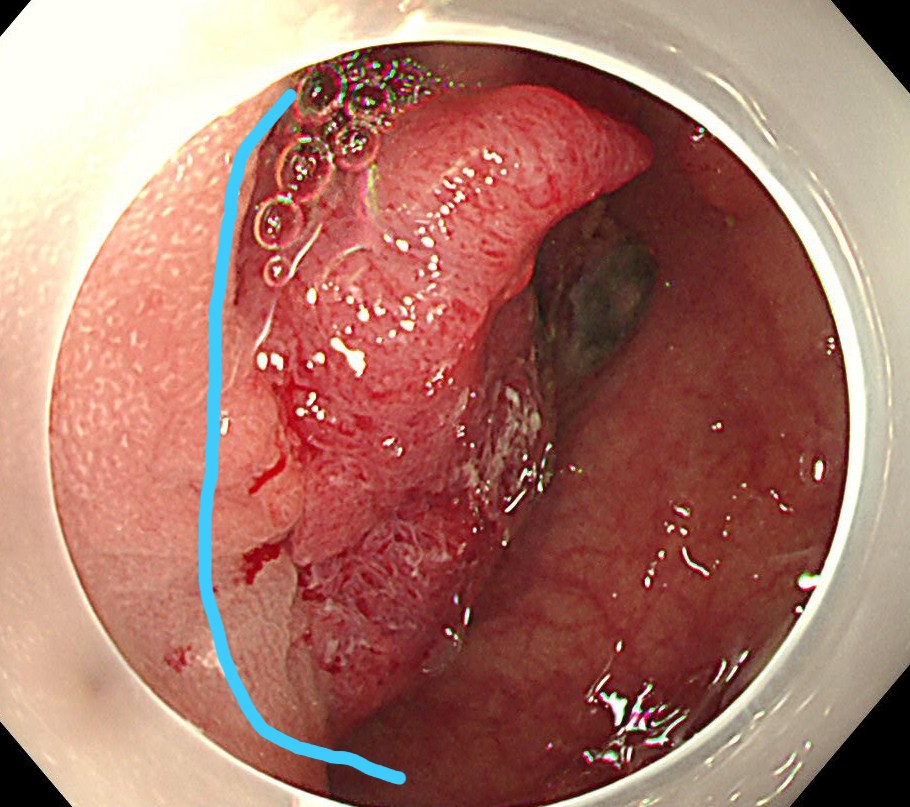

粘膜下に生理食塩水を局注し、ブルーのラインで切除します。